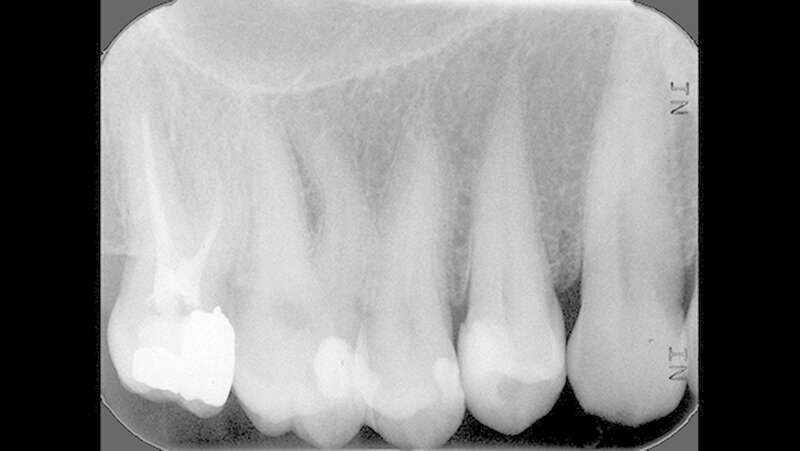

Bei den Kontrolluntersuchungen sechs und 26 Monate nach direkter Überkappung war der Zahn 14 klinisch unauffällig (Abbildung 11) und zeigte sich wiederum bei der Sensibilitätsprobe mit CO

2

-Schnee positiv und bei der Perkussionsprobe negativ.

Auf dem 26 Monate nach direkter Überkappung angefertigten Zahnfilm konnten apikal an Zahn 14 keine pathologischen Veränderungen festgestellt werden (Abbildung 12). Dem Patienten zufolge war es zu keinem Zeitpunkt, zum Beispiel im Kontakt mit kalter Nahrung, Flüssigkeit oder Luft, nach der direkten Überkappung zu Beschwerden an Zahn 14 gekommen.